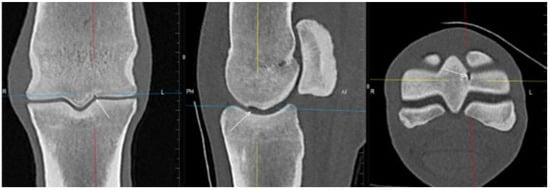

3.1. The Third Metacarpal Bone (McIII)

| Hypoattenuating lesion in the dorsal subchondral bone Subchondral bone thickening Dorsal/palmar half Increased attenuation in the trabecular bone Dorsal/palmar half Cone shaped/patchy Focal separated hyperattenuation | Hyperintense signal in the dorsal subchondral bone Subchondral bone thickening Dorsal/palmar half Decreased signal intensity in the trabecular bone Dorsal/palmar half Cone shaped/patchy Focal separated intermediate/low signal intensity | Radiolucent lesion Subchondral bone thickening Dorsal Increased trabecular bone opacity | |

| Medial/lateral condyle | |||

| Subchondral bone thickening Dorsal/palmar half Increased attenuation in the trabecular bone Dorsal/palmar half Hypoattenuating lesion in the subchondral bone Location | Subchondral bone thickening Dorsal/palmar half Decreased signal intensity in the trabecular bone Dorsal/palmar half Increased signal intensity in the subchondral bone Location | Increased opacity in the trabecular bone Lucent lesion in the subchondral bone Location | |